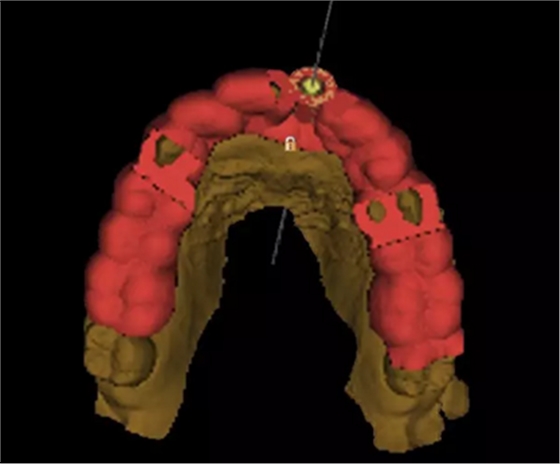

2.術(shù)前植體設(shè)計(jì)

3.術(shù)前導(dǎo)板設(shè)計(jì)